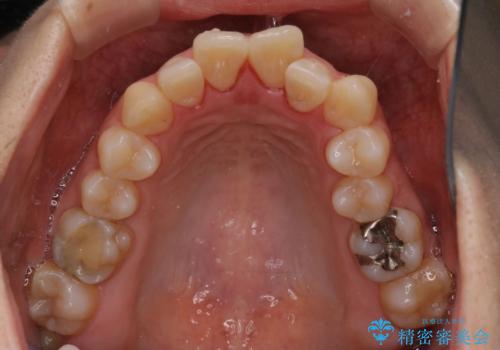

上下左右小臼歯を抜歯する治療計画を立て審美装置にて治療を行いました。

骨格的3級傾向もあり、咬合関係を仕上げるのに時間がかかりましたが、患者様には大変満足していただけました。

難しいケースでしたが、矯正用アンカースクリューを用いながら、臼歯関係もきれいに仕上げることができました。